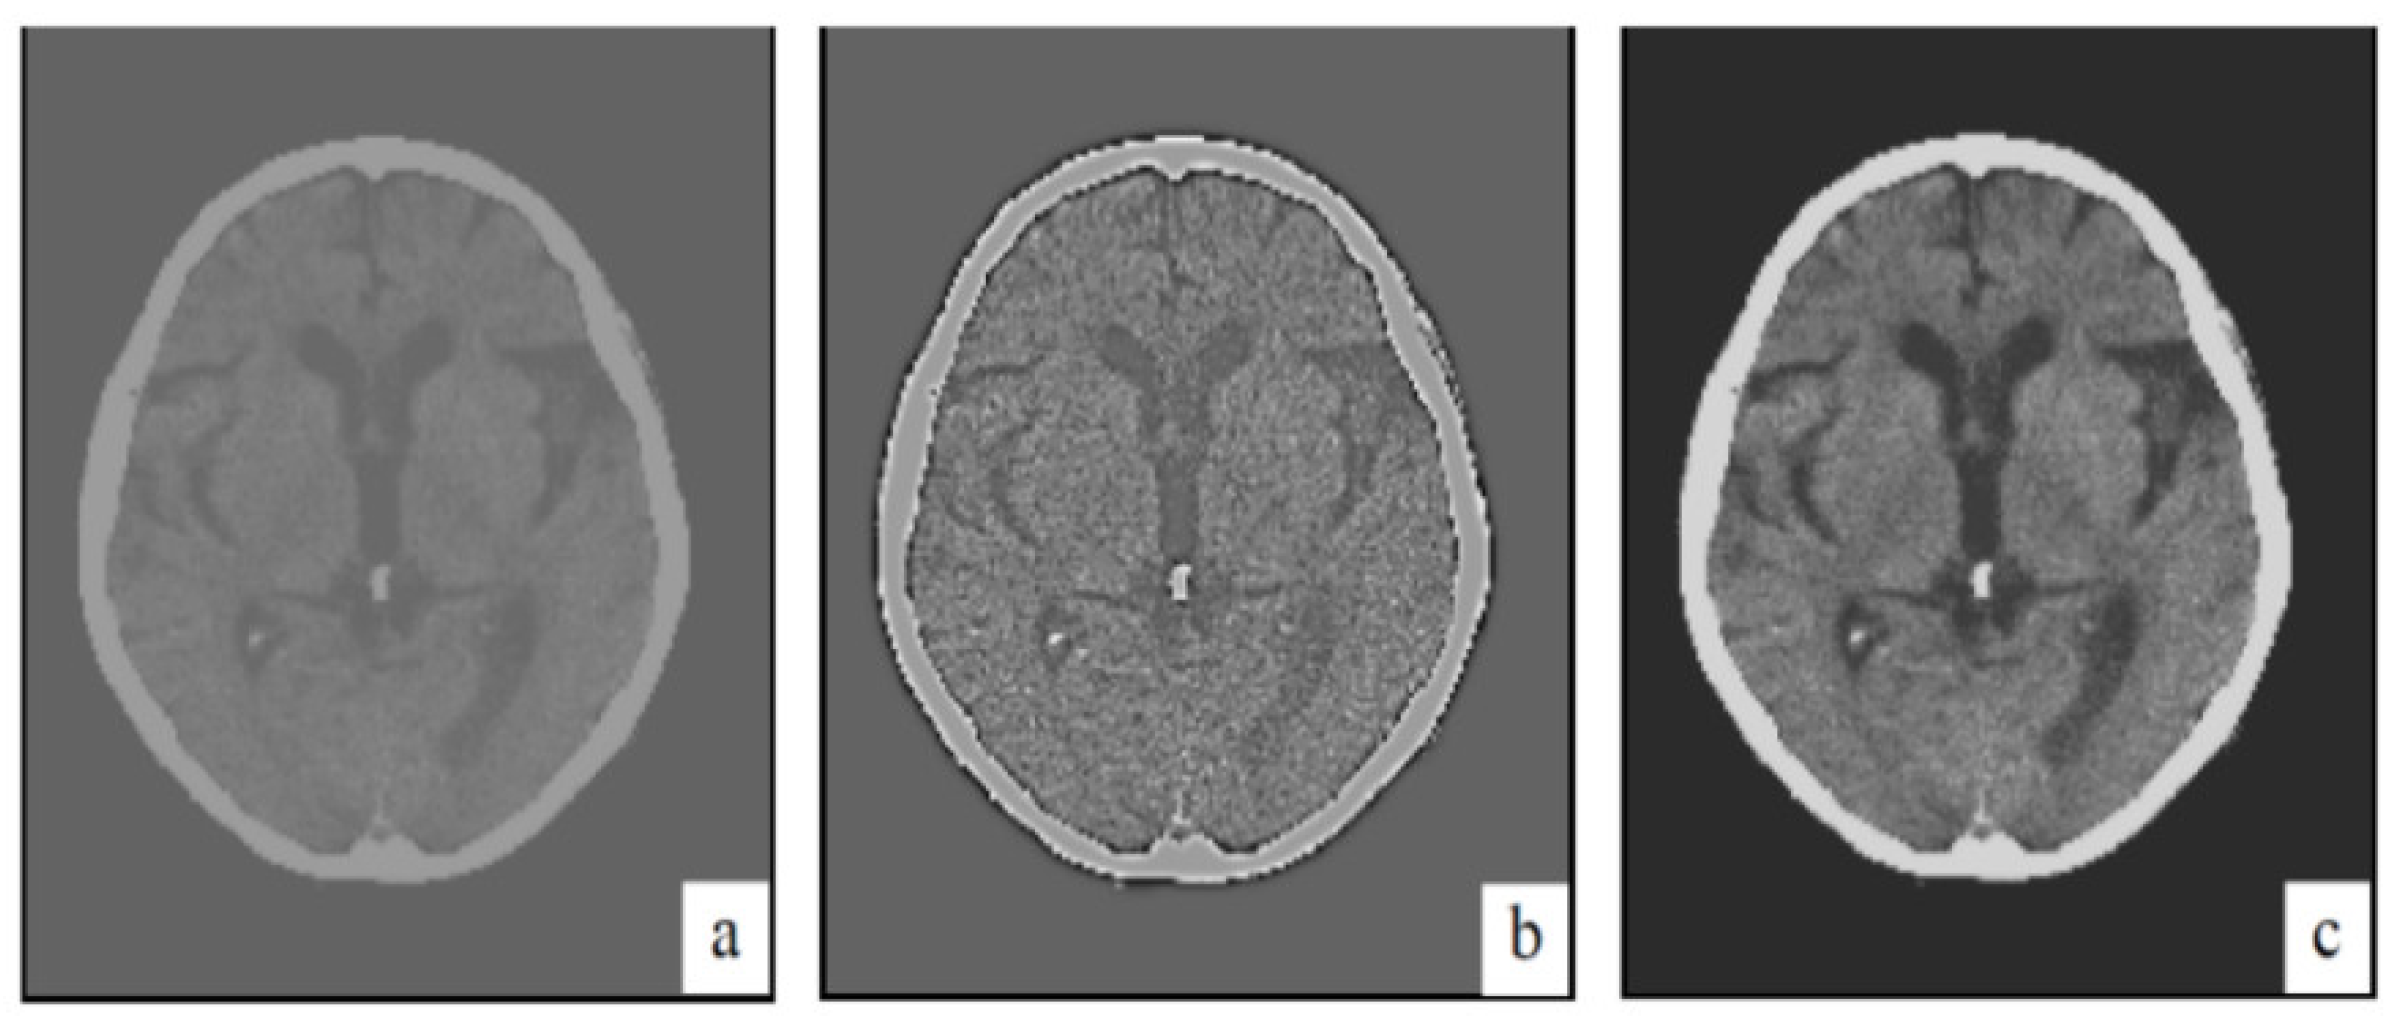

| CT image (Figure 6) 256 × 256 | 26.01 | 0.05 |

| CT image (Figure 7) 256 × 256 | 20.15 | 0.1 |

| CT image (Figure 8) 256 × 256 | 20.13 | 0.1 |

| CT image (Figure 9) 256 × 256 | 26.09 | 0.05 |

| CT image (Figure 10) 256 × 256 | 20.18 | 0.1 |

| CT image (Figure 11) 256 × 256 | 26.15 | 0.05 |